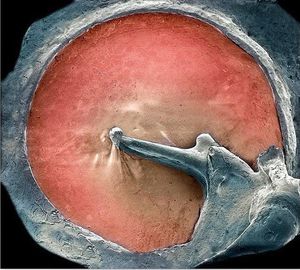

You haven't seen your EARDRUM as detailed as that before! And it looks awesome :) Coloured scanning electron micrograph (SEM) of an eardrum (red). The eardrum, or tympanic membrane, is located in the middle ear. It joins the inner ear through three tiny bones called the ossicles (malleus, incus and stapes). The malleus (centre) is attached to the inner eardrum. It articulates with the incus (right), which, in turn, links to the stapes (not seen). The middle ear transforms sound into vibrations in the fluid of the inner ear, which are then sent as nerve signals to the brain.This procedure enables you to process the sonic waves of whatever hits your ear and therefore recognize voices, noise or music.